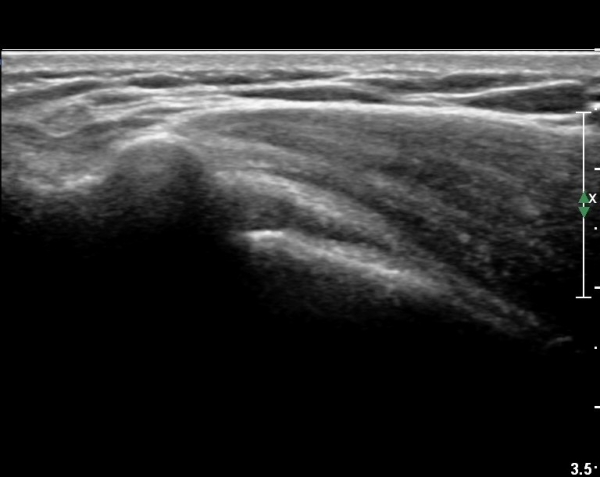

¿À±¸µ¹±â°ßºÀÀδë Á¾´Ü¸é°Ë»ç¿¡¼­ ƯÀÌ ¼Ò°ßÀ» º¸ÀÌÁö ¾ÊÀ¸³ª(»çÁø 1)

ŽÃËÀÚ¸¦ ¾à°£ °ßºÀ ¸»´ÜÀ¸·Î ³»¸®³ª ¿À±¸µ¹±â°ßºÀÀδëÀÇ ¼®È¸È­°¡ °üÂûµÈ´Ù(»çÁø 2).